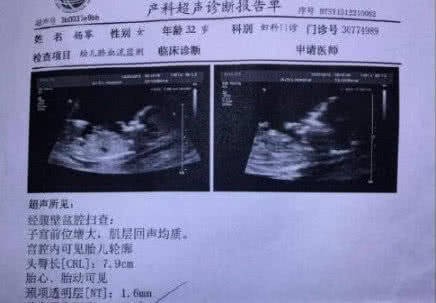

Trên mạng cũng xôn xao hình ảnh được cho là ảnh siêu âm của Dương Mịch. Thậm chí còn có những thông tin cho rằng đứa trẻ mà Dương Mịch mang thai chính là con của Lý Dịch Phong.

Tuy nhiên, trên thực tế, theo dõi tình trạng công việc gần đây của Dương Mịch thì có vẻ như thông tin này hoàn toàn giả mạo. Thực chất, tin đồn này xuất phát từ ngay thời điểm Dương Mịch ly hôn và nhanh chóng bị phủ nhận, hình ảnh siêu âm cũng được chứng minh là giả.